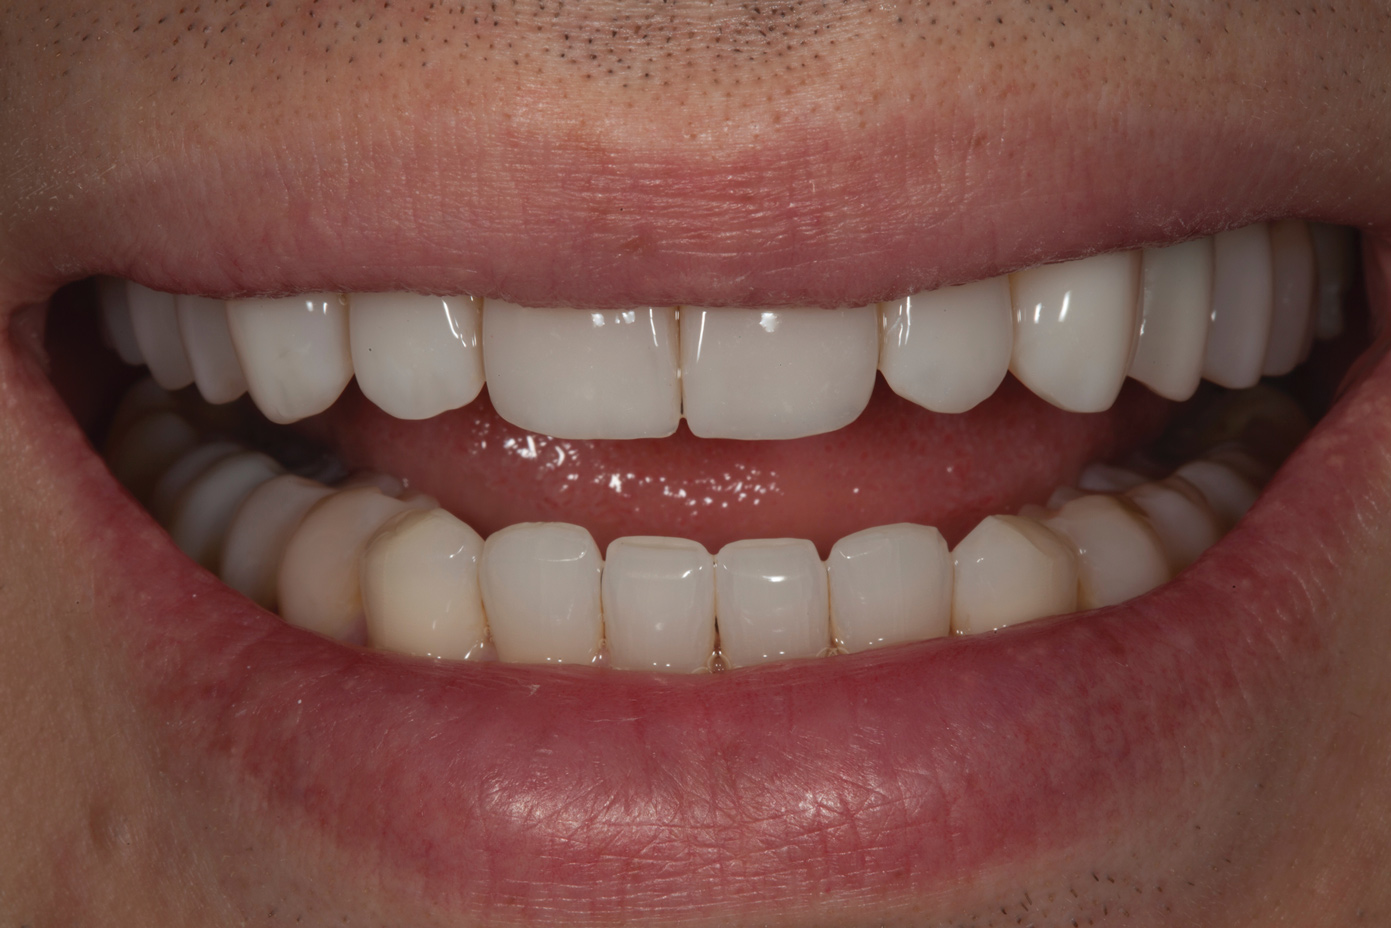

Fig 10. Postoperative smile photograph.

Figure 10

Fig 11. Postoperative retracted view.

Figure 11

Following caries treatment and tooth preparation (Figure 6), teeth Nos. 4 through 13 were restored with direct composite veneers in stages (Figure 7 through Figure 9). Using a hybrid composite for the lingual shelf and dentin layer provides wear resistance and strength for the restoration.14,15 (The lowest wear rates for restorations and the opposing dentition occur with metal alloys, machined ceramics, and microfilled hybrid resin composites. Any adjusted and unpolished porcelain surface would elicit the most wear on the opposing teeth.11)After the composite veneers were finalized, a monolithic lithium disilicate crown was placed on tooth No. 12 during a subsequent appointment, and occlusal equilibration was carried out. Final photographs were taken a couple of weeks later (Figure 10 through Figure 14).

The use of transitional bonding techniques can allow complex cases to be treated in a cost-effective and timely manner. Furthermore, occlusal and esthetic designs can be evaluated while the maximum amount of tooth structure is conserved.